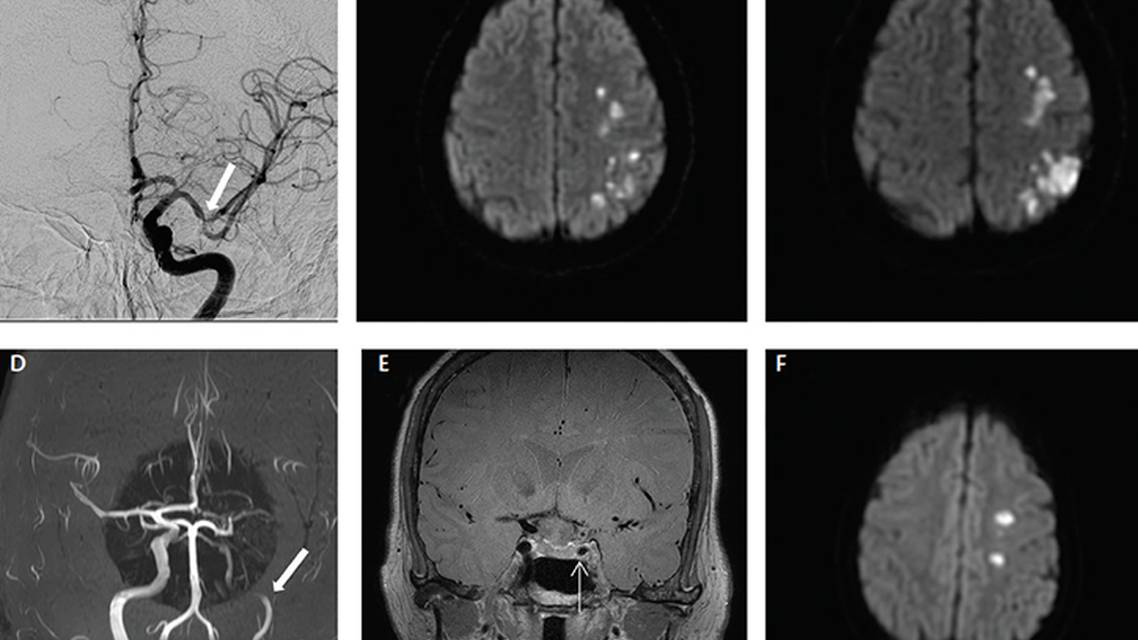

Imaging studies will show infarction in most cases of VZV vasculopathy. Commonly, a brain MRI shows lesions in the gray-white matter junction. Vessel imaging typically shows beading with areas of narrowing and poststenotic dilatation (Figure 1). Aneurysm and hemorrhage can also be seen. Pathologically, VZV has been characterized by transmural inflammation with multinucleated giant cells and epithelioid macrophages. There are no large controlled trials to guide the optimal treatment of VZV vasculopathy. Empiric intravenous acyclovir (10 mg/kg every 8 hours) for 14 days has been suggested. Corticosteroids could be considered but are not proven of benefit.

Coccidioides immitis is a soil-based fungus endemic in the southwestern US. Coccidioidomycosis can cause meningitis and vasculitis. In a retrospective study of 62 individuals with coccidioidal meningitis, almost 40% had infarction on brain imaging and nearly all died.16 An example of stroke in the setting of Cocidioides is shown in Figure 3. Neuroimaging and pathologic studies have shown that the basal ganglia, internal capsule, and pons are particularly vulnerable to infection.8 The mechanism of stroke is similar to other meningitides with perivascular and meningeal inflammation causing a vasculitis with associated intimal proliferation and vessel thrombosis. High dose fluconazole is first-line treatment for Coccidioes immitis meningitis.